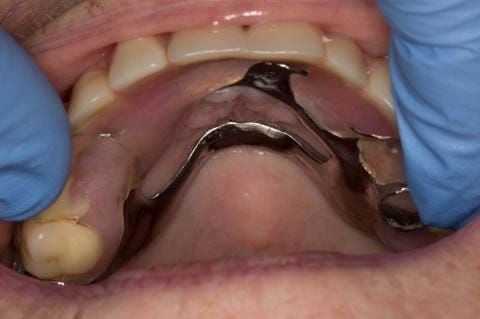

- Poorly fitting cobalt chromium based maxillary partial denture, which has been added to. This exhibited poor retention, stability and tissue fit (support). Unable to wear a new acrylic based denture.

- Cobalt chromium reinforced gasket denture - using a Molloplast B "O" ring to retain and stabilise the denture. This was my professional preference as this was the least invasive and simplest solution to this dental problem. Should the UR7 require removal in the future - an artificial tooth could be added - resulting in a complete denture. The patient would have adapted to the denture fully by this stage and have good neuromuscular control of the prosthesis.